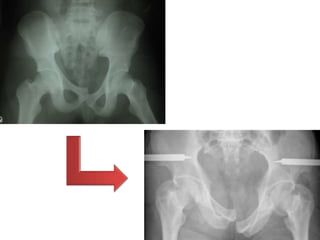

UNSTABLE PELVIC FRACTURES

• Initial survival depend on prevention of

death from hemorrhage

adequate replacement for blood

lost, and control ongoing bleeding

• Disruption of the posterior osseus-

ligamentous (sacroiliac, sacrospinous,

sacrotuberous)

• Unstable injury characterized by the type

of displacement as:

– Rotationally unstable

Imaging

Plain radiography

• Unstable fractures characterized by

– Hemipelvic cephalad

displacement that exceeds 0.5

cm SI diastasis that exceeds 0.5

cm.

– Findings suggestive of pelvic

instability include cephalad

hemipelvic displacement less

than 1 cm and/or a diastatic

fracture of the sacrum or ilium

less than 0.5 cm.

Treatment

• Hemodynamically unstable aggressive resuscitation and

prevention of further hemorrhage.

• External fixation is indicated in a hemodynamically

unstable patient with an unstable pelvic fracture.